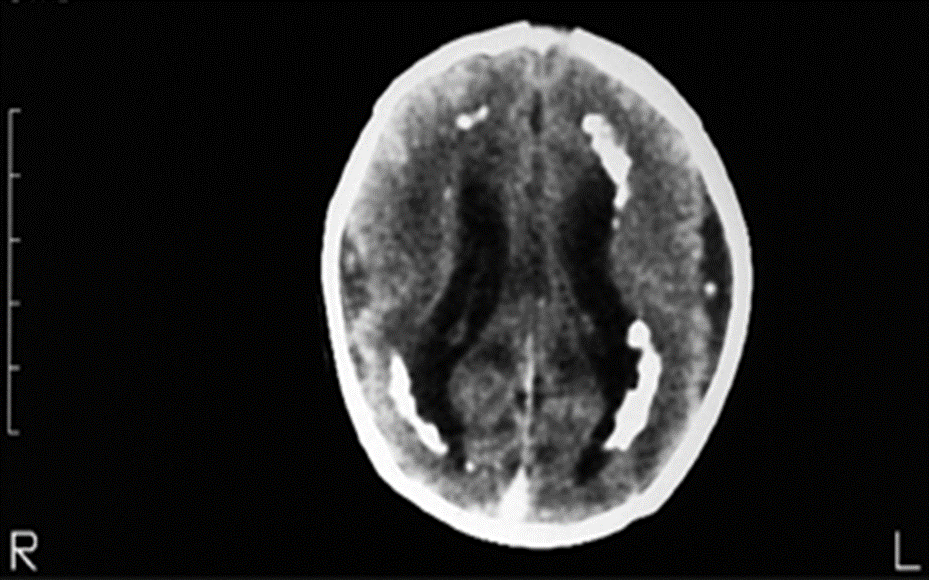

–თანდაყოლილი ინფექცია (მაგ., ტოქსოპლაზმოზი, ციტომეგალოვირუსი) – ქალასშიდა კალციფიკაციები (უკეთესად ვლინდება კომპიუტერული ტომოგრაფიით) (სურათი 4).

სურათი 4.

თანდაყოლილი ციტომეგალოვირუსული ინფექციის დროს ქალასშიდა კალციფიკაციების კომპიუტერული ტომოგრაფია

თანდაყოლილი ციტომეგალოვირუსული დაავადებით და ცენტრალური ნერვული სისტემის დაზიანებით დაბადებული ჩვილის ინტრაკრანიალური კომპიუტერული ტომოგრაფია. სკანირება აჩვენებს კლასიკურ ხაზოვან პერივენტრიკულურ კალციფიკაციებს და კორტიკალურ ატროფიას. ჩვილს დაბადებისას ჰქონდა მიკროცეფალია, ხოლო 8 წლის ასაკში განვითარების შეფერხებები და ძირითადი მოტორული დარღვევები.